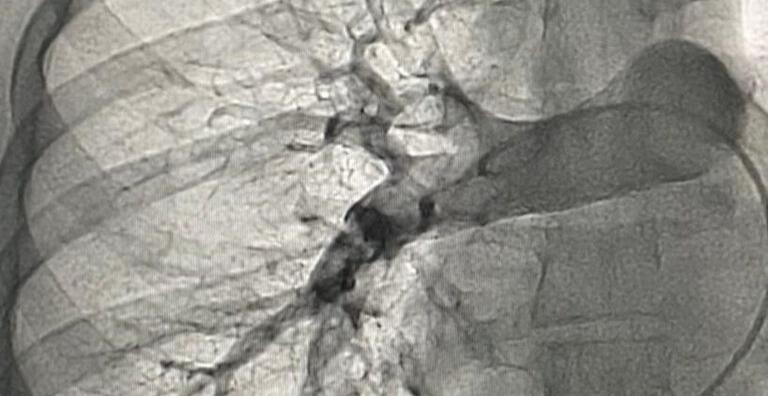

Ainda de acordo com o médico, o procedimento consistiu em inserir um cateter por meio de uma veia da perna que deu acesso diretamente ao interior da artéria pulmonar. Dessa forma, foi possível quebrar o coágulo de sangue presente na região e aspirar de forma imediata, assim restabelecendo o fluxo de sangue normal no pulmão.

Já a segunda paciente que passou pelo procedimento, poucos dias depois da primeira trombectomia no serviço, foi uma enfermeira de 29 anos que apresentava dor torácica e cansaço intenso. Neste caso, foi realizado trombolítico intrapulmonar seguido de trombectomia mecânica com aspiração de trombos.O procedimento foi concluído com sucesso sem intercorrências.

Segundo Jeann Santiago, Maria Alves foi diagnosticada com câncer de ovário, e, após passar por uma cirurgia para a remoção do tumor, desenvolveu uma trombose pulmonar no pós-operatório. A doença foi diagnosticada após realização de uma tomografia de tórax com protocolo para tromboembolismo (formação de um coágulo, que é o sangue em forma sólida, dentro da veia) pulmonar de urgência.